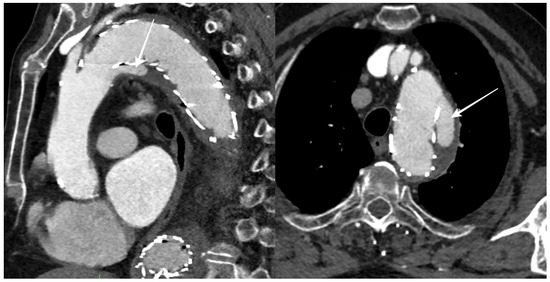

2.2. Diameter Measurement from 2D CTA Imaging

- Proximal neck (native aorta between the origin of the left subclavian artery and the proximal landing zone of the stent graft);

- Proximal landing zone of the stent graft;

- Aneurysm;

- Distal landing zone of the stent graft;

- Distal neck (native aorta between the distal landing zone of the stent graft and the origin of the celiac trunk).